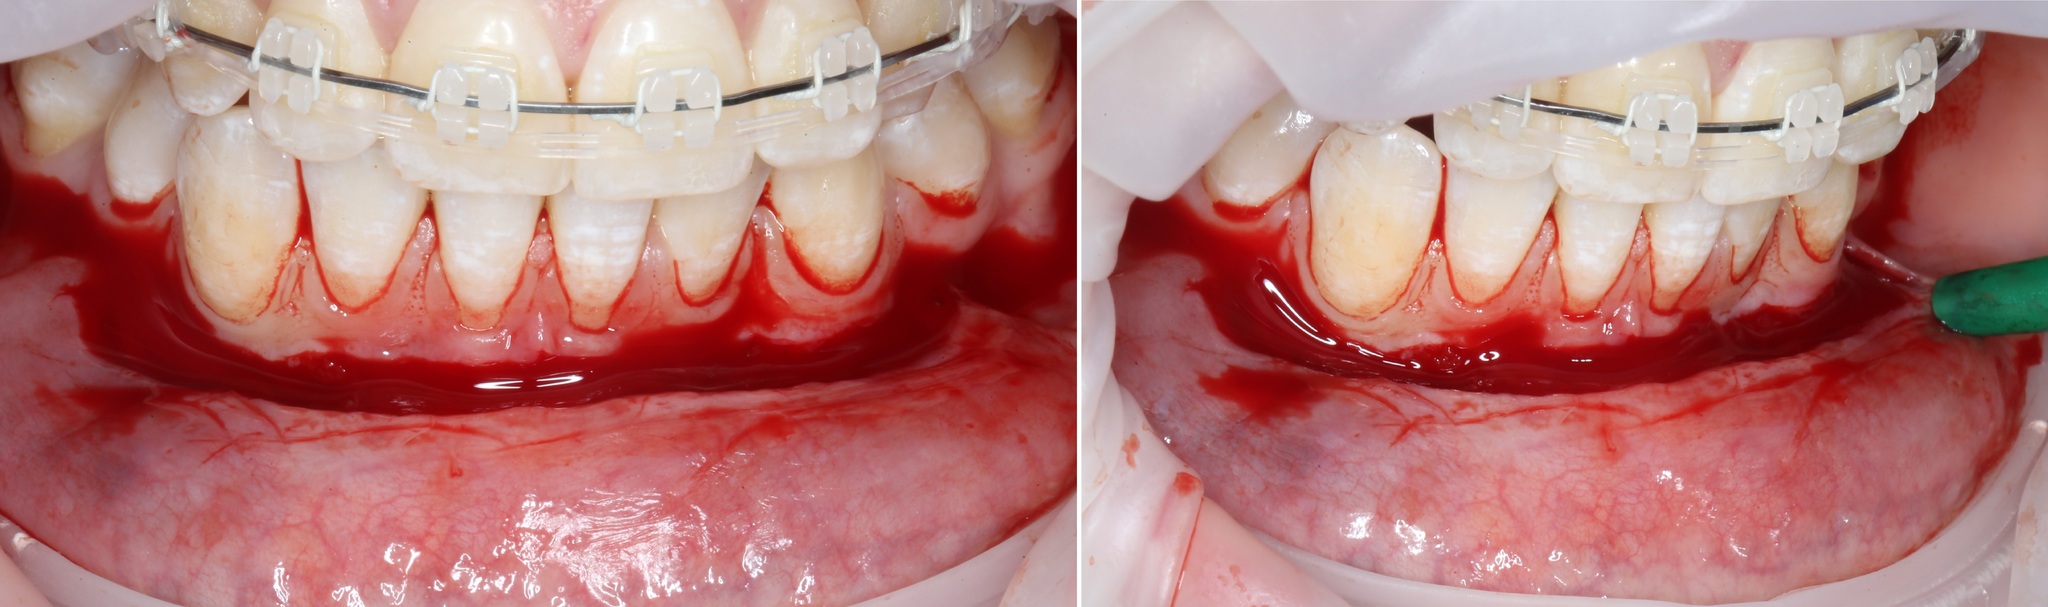

Получив аппетитную картинку для «Ганнибала», необходимо подшить ту часть, которую мы сместили вниз к надкостнице:

Такие швы необходимо наложить в нескольких местах для фиксации слизистой: